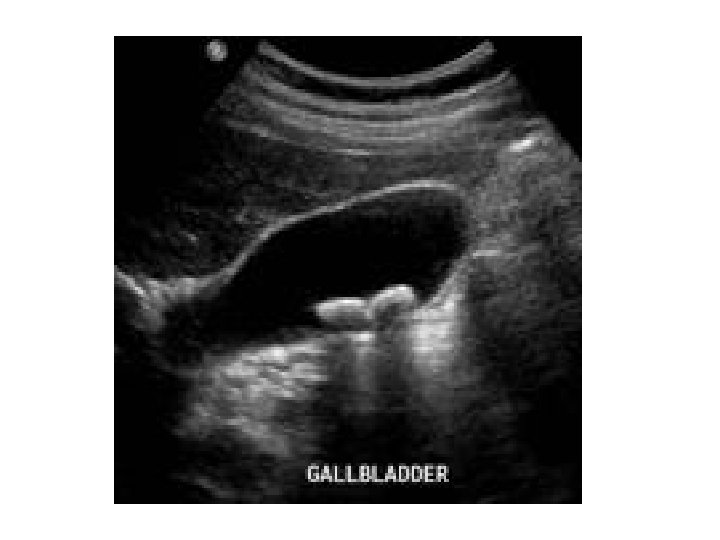

Gallstones • Hyperechoic area casting a posterior acoustic shadow. • Risk factors : obesity, drugs, ileal diseases, ileal resection, parasitic infection(ascariasis) • Cholesterol, Pigment and Mixed gall stones • Cholecystectomy